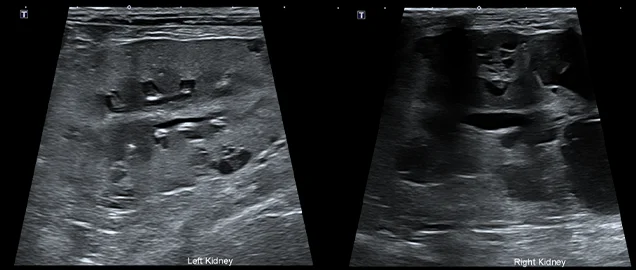

• 만성 신부전 및 유전성 신장 질환 환자

구토, 기력 저하, 식욕 절폐 등을 주증으로 내원. 혈액 검사상 심각한 수준의 azotemia(질소혈증)가 확인되었습니다.

초음파 검사에서는 신장의 피질과 수질이 구분되지 않고, 실질 내 다수의 낭종이 있는 형태학적 변화가 확인되어 유전적 신장 기형 및 만성적인 신장 기능 저하가 있었던 것으로 의심되었습니다.

요분석 결과, 신장 기능 저하를 유발할 결석이나 세균 감염은 확인되지 않았으며, 신장 기능 저하에 의한 단백뇨 소견이 확인되었습니다.

무뇨/핍뇨 소견이 없어 우선 수액 처치와 단백뇨 및 고혈압 관련 약물 치료를 통해 신장 기능 개선 여부를 모니터링했습니다.

현재 신장 수치가 양호하게 개선되고 있으며, 정기적인 신장 수치 모니터링 및 초음파 검사를 통해 꾸준히 관리할 예정입니다.